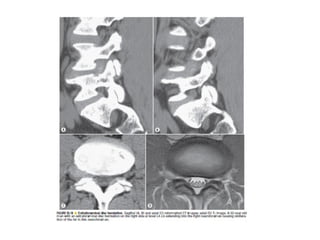

The spine is made up of vertebrae separated by intervertebral discs that allow movement and provide shock absorption. Diagnostic imaging plays an important role in evaluating the spine for conditions like fractures, disc herniations, spinal stenosis, and tumors. Imaging modalities like X-rays, CT scans, MRI, and bone scans can detect abnormalities and aid physicians in diagnosing and treating various spinal disorders.